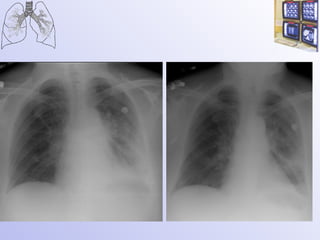

Мелкоклеточный рак легкого 8  октября 28 августа

Мелкоклеточный рак легкого 7 сентября

Мелкоклеточный рак легкого